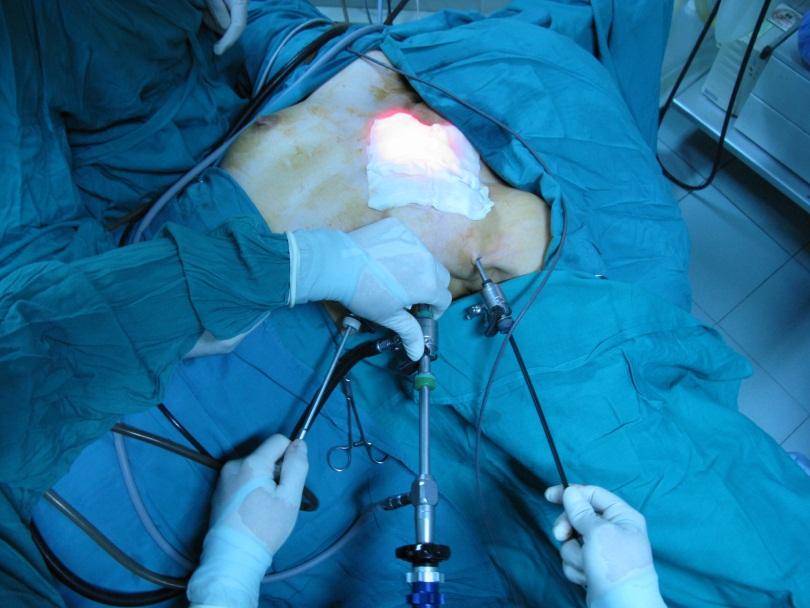

In selected patients, it may be possible to remove the thyroid gland using keyhole surgery (See Figure 5) or robotic surgery (see Figure 6) through the armpit. This clearly avoids the neck incision and is favoured by some women. It is best to seek the opinion of a surgeon if you wish to have this type of surgery.

Figure 5: Endoscopic thyroid surgery through the armpit. The author learnt this technique from Prof Luong (right) who is a leading authority on this approach